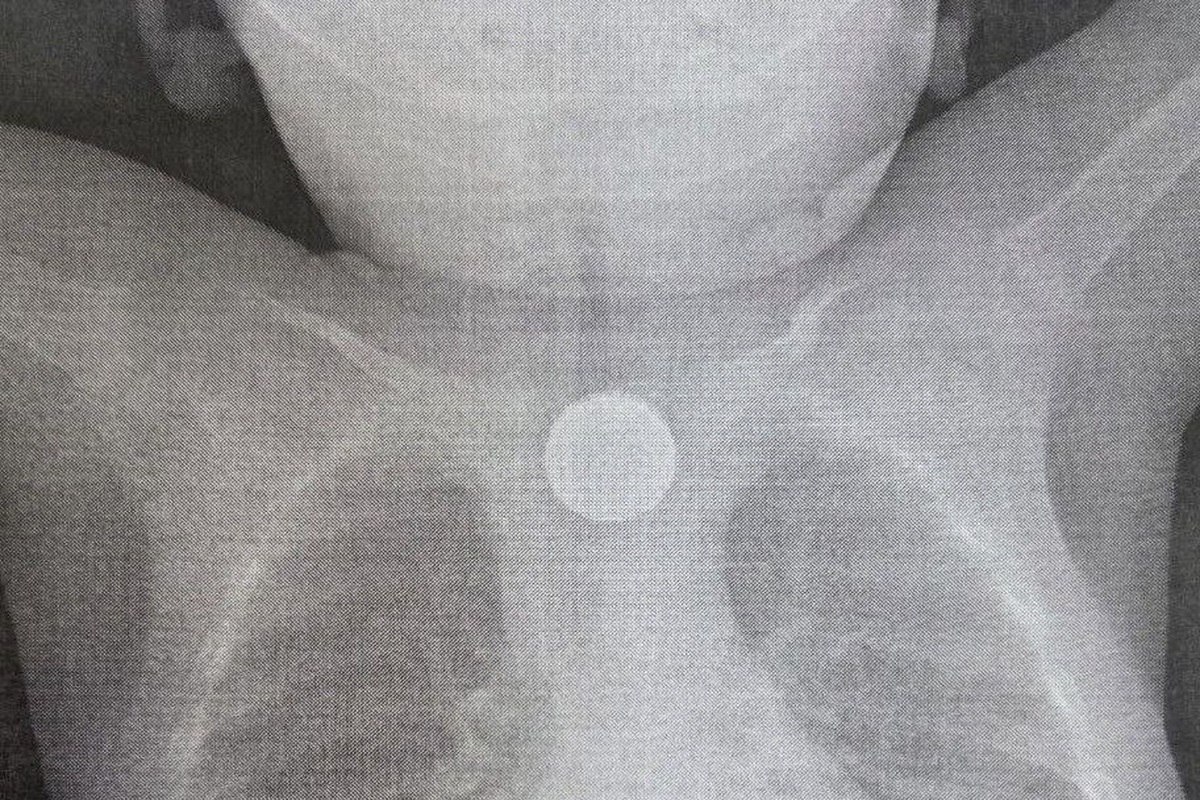

Срочная операция была проведена в Детской республиканской клинической больнице (ДРКБ) в Улан-Удэ, где медики спасли жизнь годовалому пациенту. Малыш проглотил дисковую литиевую батарейку и двухрублевую монету, что привело к тяжелейшему химическому ожогу пищевода.

Поводом для обращения за медицинской помощью стало резкое ухудшение состояния ребенка 27 ноября. У малыша началась многократная рвота, а спустя два часа поднялась температура и появились хрипы при дыхании. После осмотра в центральной районной больнице, где было диагностировано инородное тело в пищеводе, ребенка экстренно направили в ДРКБ, рассказали в учреждении здравоохранения.